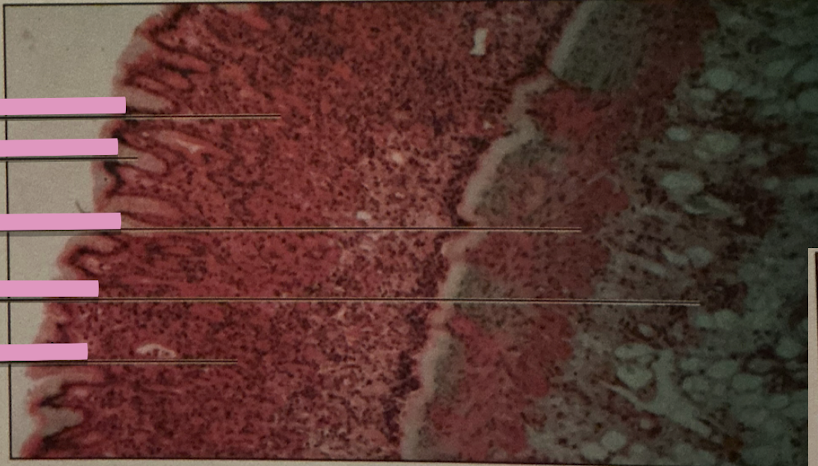

stomach at 40x

stomach at 100x

gastric pits

exocrine ducts from glands that lead to stomach lumen

gastric glands

exocrine epithelia secrete mucus, gastric acid, intrinsic factor, peptic cells, neuroendocrine cells, and stem cells

duodenum

brunner’s glands

intestinal epithelium

duodenum

________ receives chyme when stomach empties; exocrine release site for gallbladder & pancreatic secretions

intestinal glands

secrete mix of sucrase, maltase, & peptidases + definsins & enzymes

brunner’s glands

produce mucus-rich alkaline secretion to protect from acidic content, lubricate walls, & enable absorption

goblet cells

single-celled exocrine glands secrete mucus